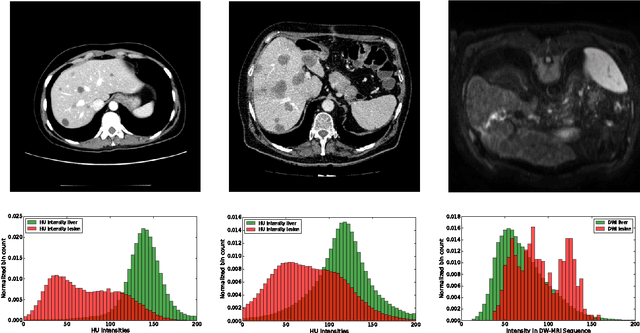

Abstract:Automatic segmentation of the liver and hepatic lesions is an important step towards deriving quantitative biomarkers for accurate clinical diagnosis and computer-aided decision support systems. This paper presents a method to automatically segment liver and lesions in CT and MRI abdomen images using cascaded fully convolutional neural networks (CFCNs) enabling the segmentation of a large-scale medical trial or quantitative image analysis. We train and cascade two FCNs for a combined segmentation of the liver and its lesions. In the first step, we train a FCN to segment the liver as ROI input for a second FCN. The second FCN solely segments lesions within the predicted liver ROIs of step 1. CFCN models were trained on an abdominal CT dataset comprising 100 hepatic tumor volumes. Validations on further datasets show that CFCN-based semantic liver and lesion segmentation achieves Dice scores over 94% for liver with computation times below 100s per volume. We further experimentally demonstrate the robustness of the proposed method on an 38 MRI liver tumor volumes and the public 3DIRCAD dataset.